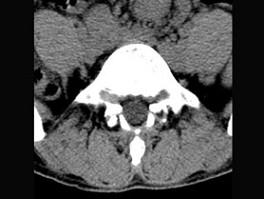

问题 男,29岁,腰痛伴下肢轻度麻木,有外伤史,请结合所提供图像,选择最佳答案 ( )

选项 A、S向后滑脱 B、未见异常 C、L向后滑脱 D、S向前滑脱 E、L向前滑脱

答案 E